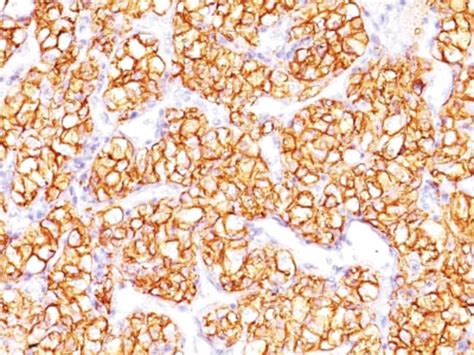

Renal Cell Carcinoma (PN-15)